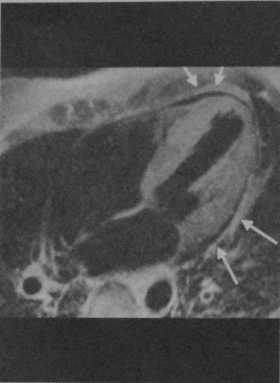

Плазмоцитома и амилоидоз сердцау женщины 60 лет. Т1 -взвешенная последовательность с подавлением жировой ткани с темнойкровью GE: Четырехкамерный срез демонстрируетвыраженную гипертрофию миокарда во всех участках стенки. Стрелки показывают разделение слоевперикарда в связи с наличием перикардиальноговыпота.

Последовательность обратного восстановления GE после введения Gd-DTPA. Четырехкамерный срез демонстрирует диффузное усилениевсех участков стенки.